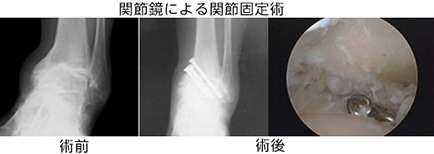

手術療法はそれぞれの部位・変形の程度に応じて、関節温存を目的とした骨切り手術、除痛・変形矯正のための関節固定術、人工関節置換術などが選択されます。

しかし、変形の強い変形性足関節症では、長期にわたり、痛みを確実に取り除くために、手術療法が必要となります。手術療法は関節固定術や関節温存手術、人工関節などがあります。我々は、リング型創外固定を使用した骨切り術による関節温存手術を積極的に行っています。末期の変形性関節症の方に対して関節固定術においても、関節鏡を用いた方法を行うことで侵襲を小さくする方法を行っています。また患者さんの状態に応じて、人工関節手術も行っています。